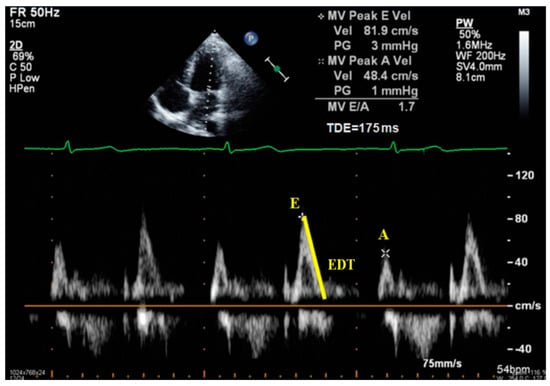

- Peak of passive filling (E wave), peak of active filling (A wave), E/A ratio, deceleration time of E wave (EDT) with pulsed Doppler (Figure 3);